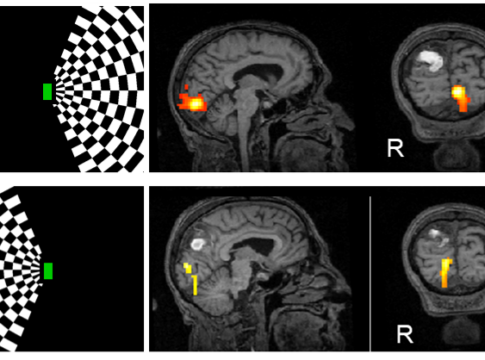

Un AVC focal entraîne souvent une activation asymétrique des circuits perceptifs et moteurs dans l’hémisphère endommagé, même dans les circuits anatomiquement intacts. Cela conduit à un syndrome de négligence spatiale unilatérale dans lequel les patients ne parviennent pas à diriger leur attention vers un côté de l’espace.

• Les patients victimes d’un AVC effectuent des tâches visuelles pendant lesquelles nous enregistrons leur activité cérébrale en temps réel à l’aide de méthodes de neuroimagerie fonctionnelle telles que l’électroencéphalographie (EEG) ou l’imagerie par résonance magnétique fonctionnelle (IRMf).

Rétablir une activité cérébrale symmétrique

• Lorsqu’une lésion cérébrale entraîne une activation plus faible des circuits cérébraux dans l’hémisphère affecté par un AVC, les patients utilisent le neurofeedback pour rétablir une activation plus symétrique dans les deux hémisphères.

• L’augmentation de l’activation des circuits affaiblis par l’AVC améliore la transmission des informations perceptives et motrices dans l’hémisphère endommagé et rétablit la capacité à diriger l’attention vers les deux côtés de l’espace.